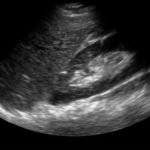

FAST Exam: Normal Morrison’s Pouch

FAST Exam-Normal Morrison's Pouch Still

radiology, normal, renal, Morrison’s pouch, trauma, liver, ultrasound, FAST exam

Ultrasound